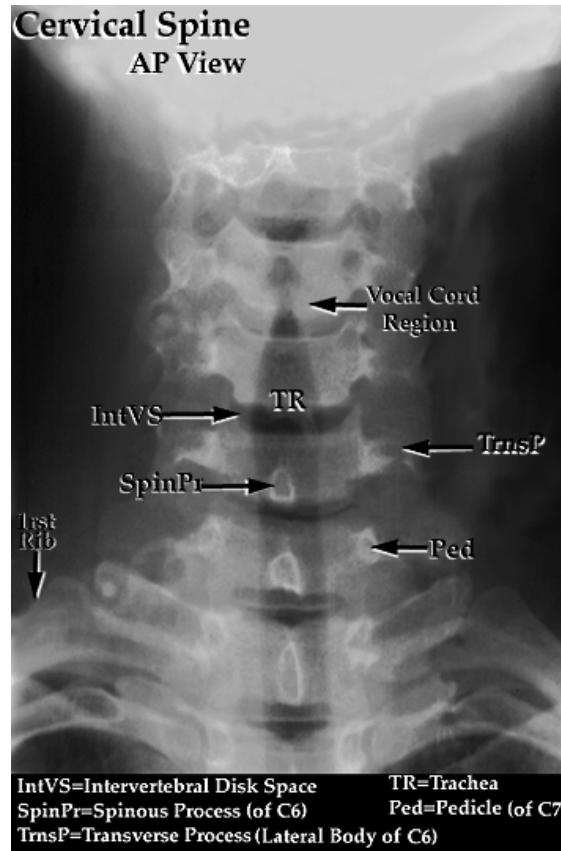

Anteroposterior (AP) View:

- Intact lateral outline

- Spinous processes & Trachea in the middle